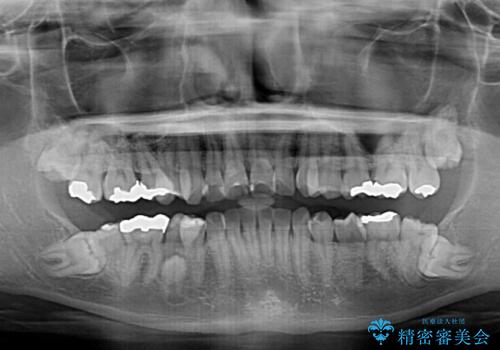

- 上の前歯の出っ歯とでこぼこの歯並びを気にして来院された患者様です。

上下顎歯列ともに前方に突出していましたが、上顎歯列がより前方位にあったため、上顎左右は第1小臼歯を、下顎左右は第二小臼歯を抜歯することとしました。

下顎は過剰歯が埋伏しており、それが原因となってスペースが閉じなかったため、途中で抜歯して速やかに仕上げました。